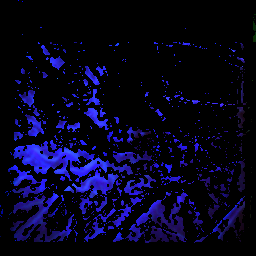

Non-responder

Unfortunately, some shots were stopped already at a point where the maximum was not reached. Therefore, it is hardly possible to evaluate them.

before the first rheopheresis after the first rheopheresis before the third rheopheresis after the third rheopheresis

time of the maximum: 93.6 f ± 17.3%

visual acuity: 0.25

time of the maximum: 74.1 f ± 14.5%

visual acuity: –

time of the maximum: 52.4 f ± 10.1%

visual acuity: 0.32

time of the maximum: 66.4 f ± 8.6%

visual acuity: 0.20